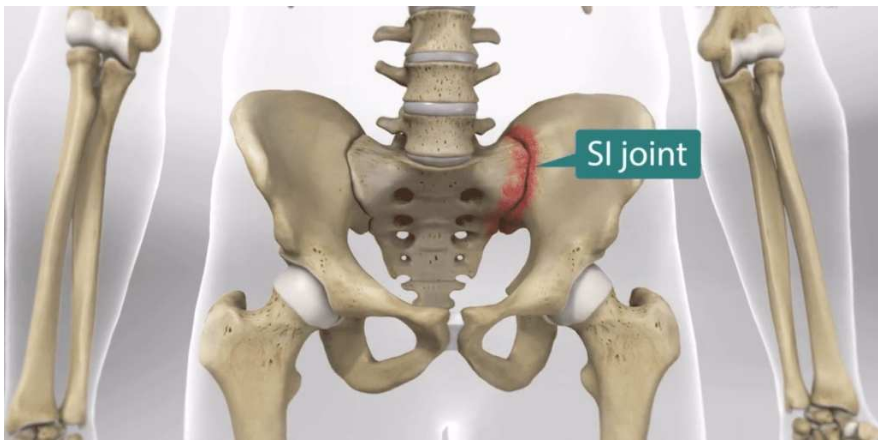

What is the route of the mesentery?

mesentry is attached to posterior abdo wall via roots - oblique course

• Duodenojejunal flexure to sacro-iliac joint